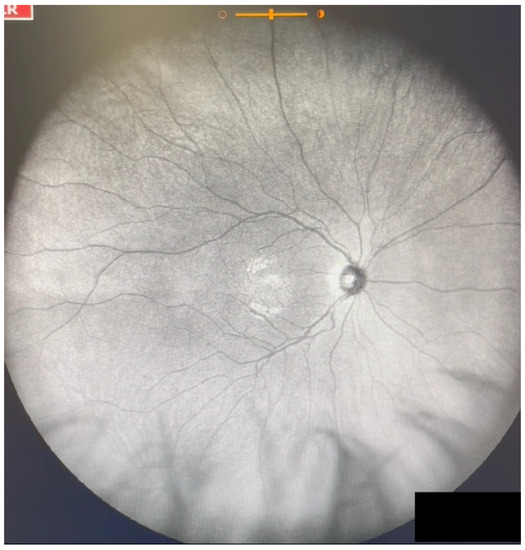

Figure 1.

Ultra-widefield IRcSLO image of an eye with Grade 0 vitreous floaters. No shadows are observed. See also Video S1.